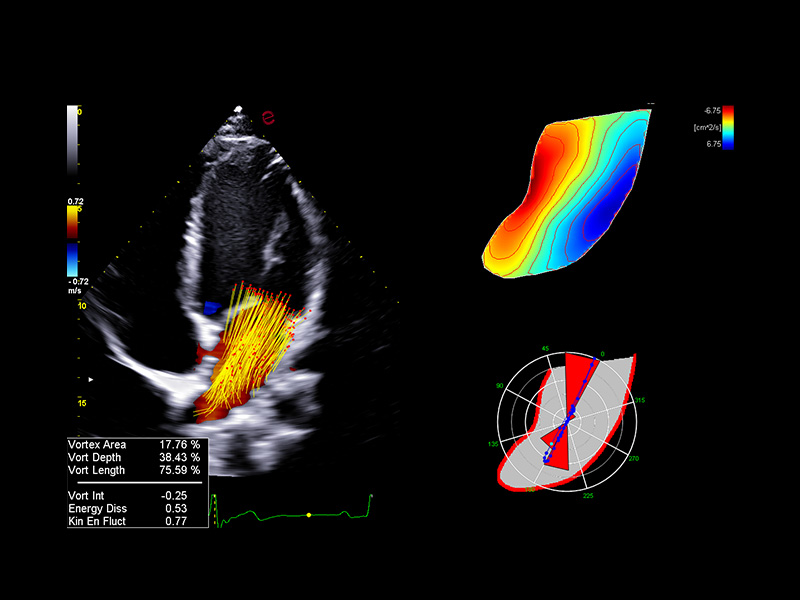

Innovative hemodynamic assessment with HyperDoppler

Esaote’s HyperDoppler technology provides an advanced visualization of intracardiac blood flow dynamics, offering clinicians an intuitive understanding of complex hemodynamics that goes beyond conventional Doppler imaging. By generating real-time vector maps, streamlines, and vortex formations, HyperDoppler enables the detailed assessment of diastolic function, ventricular dyssynchrony, and valvular abnormalities.

This unique flow visualization supports earlier detection of subtle dysfunction and increases diagnostic confidence, particularly in challenging cases such as heart failure, prosthetic valve evaluation, and structural heart disease. HyperDoppler’s zero-click, visually rich interface enables faster, more comprehensive exams, allowing cardiologists to make more informed clinical decisions.